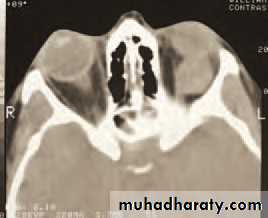

• An MRI or CT scan is helpful in diagnosis and in planning treatment (Fig. 4.2). The condition usually responds to intravenous broad spectrum antibiotics. It may be necessary to drain an abscess or decompress the orbit particularly if the optic nerve is compromised. Optic nerve function must be closely watched, monitoring acuity, colour vision and testing for a relative afferent pupillary defect. Orbital decompression is usually performed with the help of an ENT specialist.

• (b) A CT scan showing a left opaque ethmoid sinus and subperiosteal orbital abscess.